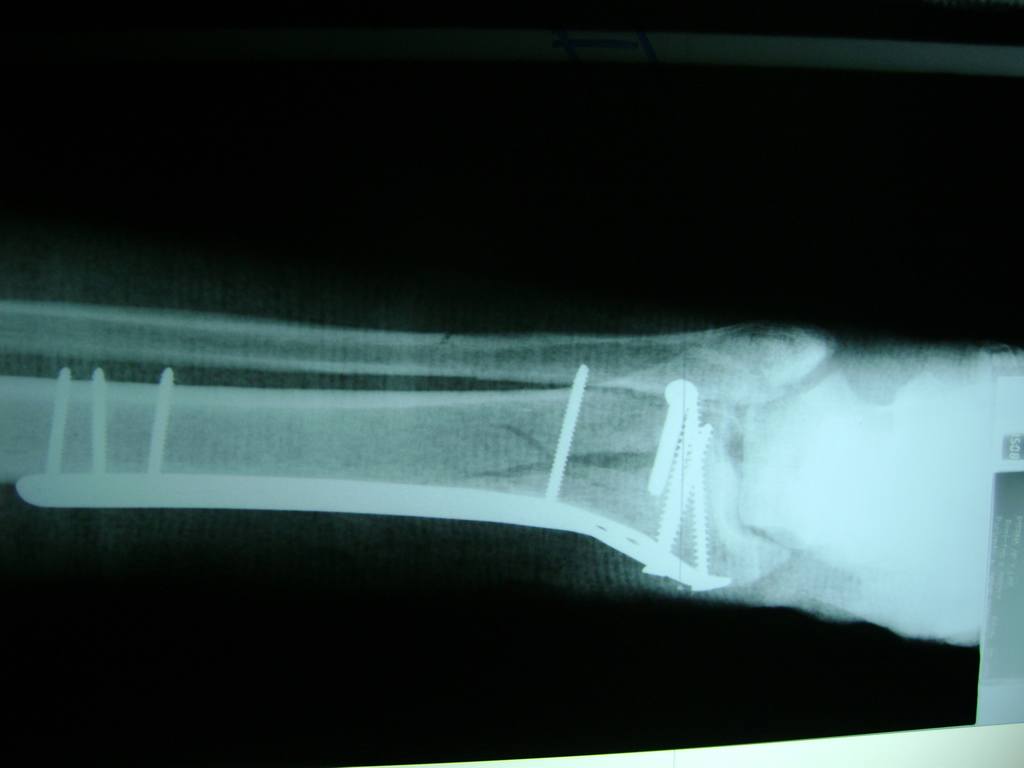

Cirugías de Calcaneo - Perone y Tibia

Aunque cada uno de estos huesos puede fracturarse por separado, normalmente la rotura es una lesión que se produce de forma conjunta

La mayor parte de las roturas implican a la parte proximal del hueso (parte del hueso próximo a la rodilla) o a la parte distal (parte del hueso cerca del tobillo).

Debido a la fina cobertura de piel que recubre la tibia y el peroné, las fracturas generalmente son abiertas, es decir, el hueso roto rasga la piel, atravesándola. Las fracturas de tibia y peroné generalmente se producen por un fuerte impacto o torsión.